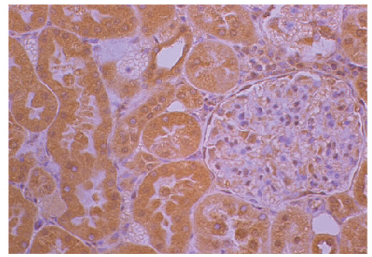

實驗示例:大鼠腎臟石蠟切片在失血30%后經酮咯酸處理,使用抗IL-1抗體進行染色,隨后使用兔抗山羊IgG(H+L)-BIOT(SB產品編號6160-08)、辣根過氧化物酶偶聯鏈霉親和素、DAB和蘇木精進行染色。

該圖像來自Guedes FS Jr、Cruz DS、Rodrigues MM、Silva LM、Amorim RL、Vianna PT等人的研究,標題為《大鼠急性失血后在七氟醚和酮咯酸作用下的腎臟組織學和免疫組化研究》,發(fā)表于《巴西外科雜志》2012年第27卷,頁碼37-42。